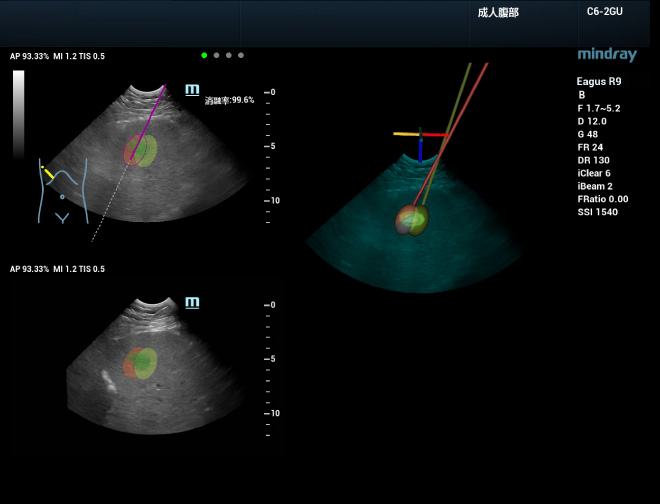

Tedavide daha yÞksek gÞven

3B ablasyon planlamas? esnas?nda, birka? i?ne ile ablasyon yap?lmas? gereken bÞyÞk lezyonlar i?in etkili bir tedavi stratejisi geli?tirilmesi amac?yla ablasyon simÞlasyonu yap?labilir. ?nce, her bir i?ne i?in ablasyon mesafesi ayarlan?r ve ard?ndan simÞlasyonda ablasyon i?neleri yerle?tirilir. Lezyonun kapsama oran?n?n ger?ek zamanl? g?sterimine bakarak, optimum bir nihai plan olu?turulabilir. Bu i?lem, tÞm?rÞn bÞtÞnÞ i?in ablasyon kapsam?n?n sezgisel ve ?ok boyutlu g?zlemlenmesine olanak tan?yan, Þ? boyutlu, ?ok a??l? g?rÞntÞlemeyi destekler. Ard?ndan i?ne, planlanan yola g?re ger?ek tÞm?re y?nlendirilebilir ve ger?ek i?ne giri?iyle, ablasyon kapsam? ger?ek zamanl? olarak gÞncellenir. uHit Fusion kullan?larak, tÞm ablasyon sÞreci daha iyi planlanabilir ve standartla?t?r?labilir, b?ylelikle operat?rÞn deneyime olan ba??ml?l??? azalt?l?r.